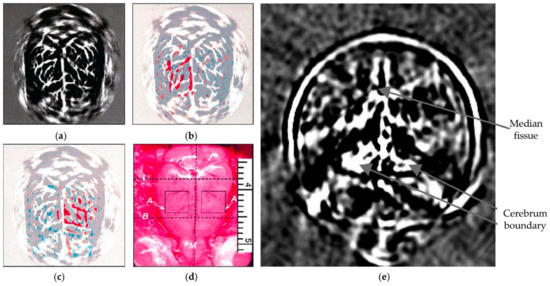

- Xu, Y.; Wang, L. Rhesus monkey brain imaging through intact skull with thermoacoustic tomography. IEEE Trans. Ultrason. Ferroelectr. Freq. Control 2006, 53, 542–548. [Google Scholar] [PubMed]